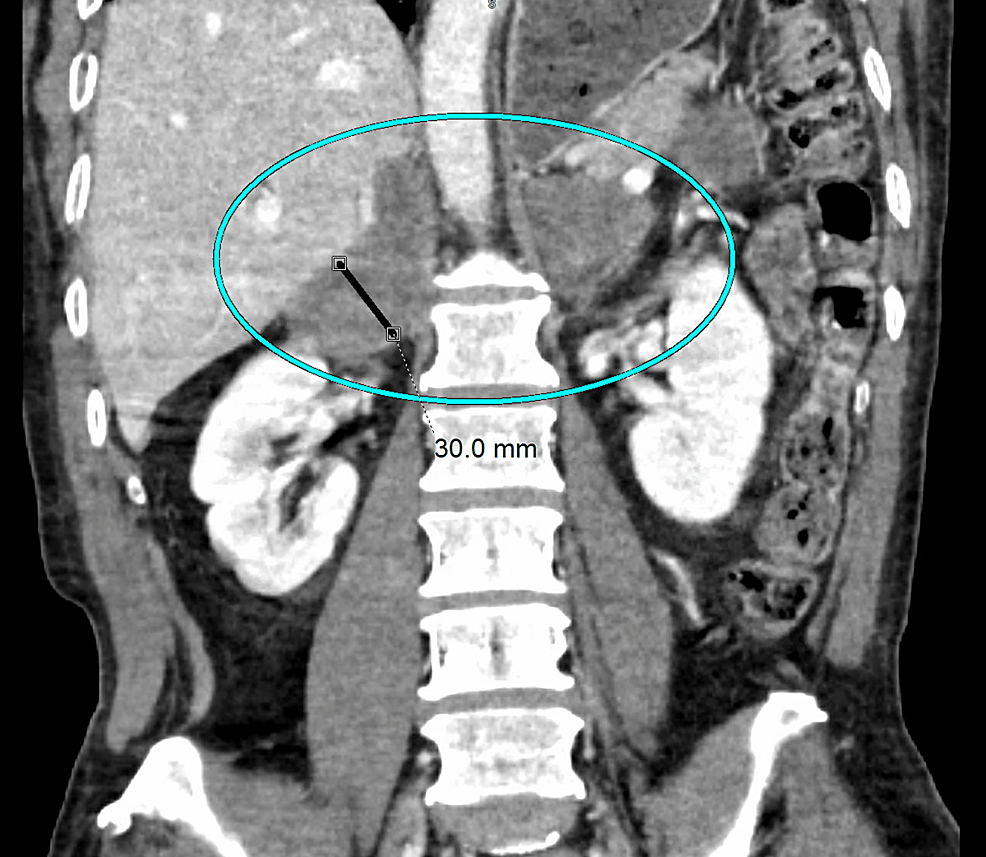

From radiopaedia.org

Adrenal histoplasmosis Image Radiopaedia Histoplasmosis histoplasmosis is a common infection in the central united states and is acquired through inhalation of airborne. Pulmonary histoplasmosis is the most. · most infections are subclinical. histoplasmosis is an endemic mycosis caused by histoplasma capsulatum. histoplasmosis is an endemic mycosis caused by histoplasma capsulatum. the ct findings of pulmonary histoplasmosis are varied and nonspecific. . Radiopaedia Histoplasmosis.

Adrenal histoplasmosis Image Radiopaedia Histoplasmosis histoplasmosis is an endemic mycosis caused by histoplasma capsulatum. the diagnosis and treatment of pulmonary histoplasmosis, as well as the pathogenesis, clinical manifestations,. · most infections are subclinical. Pulmonary histoplasmosis is the most. thoracic (or pulmonary) histoplasmosis refers to pulmonary manifestations from infection with the fungus histoplasma capsulatum. histoplasmosis is an endemic mycosis caused by histoplasma. Radiopaedia Histoplasmosis.

Adrenal histoplasmosis Image Radiopaedia Histoplasmosis thoracic (or pulmonary) histoplasmosis refers to pulmonary manifestations from infection with the fungus histoplasma capsulatum. · most infections are subclinical. the diagnosis and treatment of pulmonary histoplasmosis, as well as the pathogenesis, clinical manifestations,. histoplasmosis is an endemic mycosis caused by histoplasma capsulatum. histoplasmosis is an endemic mycosis caused by histoplasma capsulatum. the ct findings. Radiopaedia Histoplasmosis.